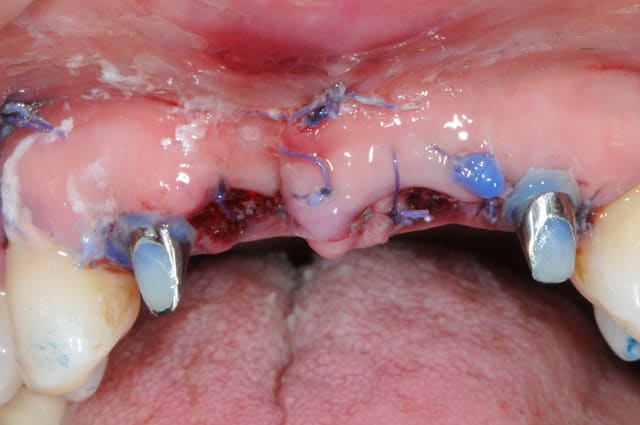

la ROG maintenant... ou "comment essayer de sauver les meubles"

Puisque tu as voulu gérer en extraction implantation ce cas délicat avec une perte osseuse pourquoi avoir fait un lambeau ?

Une technique sans lambeau (avec comblement osseux des gap sur 12 et 22 et pourquoi pas des alvéoles de 11/21) me semblait plus appropriée pour réduire la perte osseuse et gingivale ainsi qu'une fermeture des sites de 11 et 21 à l'aide d' un greffon epithélio conjonctif circulaire.

A ta place j'attendrai que les implants soient ostéo intégrés avant de tenter quoique ce soit: ROG ou greffe conjonctif enfoui ...